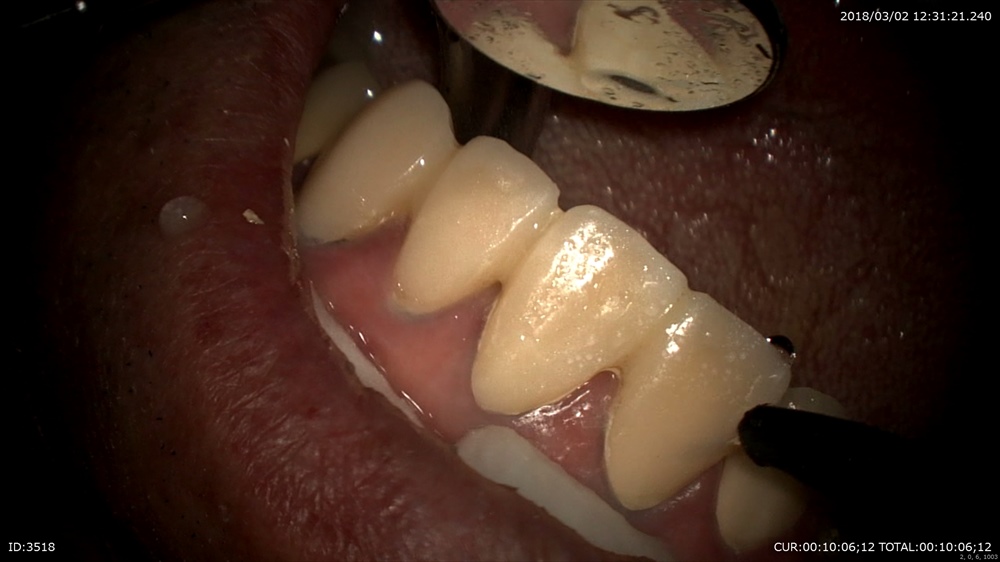

綺麗に。前歯ですから抜いてインプラントは難易度が上がります。

お薬

仮歯も封鎖性の良いもので

この様に重症の虫歯でも諦めないのが当院です。